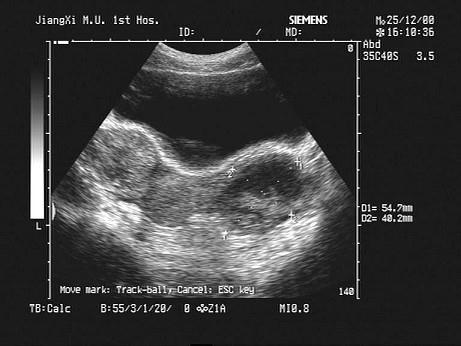

问题 女性,48岁,取环术后3天,述左下腹疼痛。B超检查如图,最可能的诊断为?(?)

选项 A.畸胎瘤 B.盆腔血肿 C.子宫浆膜下肌瘤 D.宫外孕 E.附件囊肿

答案 B